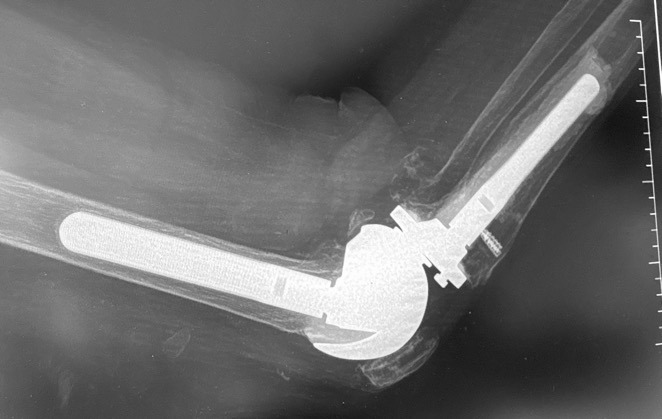

This is 74-year-old female, with a BMI of 33 kg/cm2, and multiple comorbidities (CHF, Arrhythmia, anxiety, 3 previous surgeries of the knee). She presented three months status post patellar tendon rupture, patellar fracture and dislocation. The patellar fracture was fixed with a wire, and in the radiograph you can see the anchor suture in the tibial tubercle area, the wire below the tubercle, within the gutters, and threaded above the patella. (Figure 8)

We removed the wire about six months following repair. At that time, she had ROM for 0-95 degrees. At six years out following repair she walks with no ambulatory aids and has full extension. (Figures 9, 10A-C)